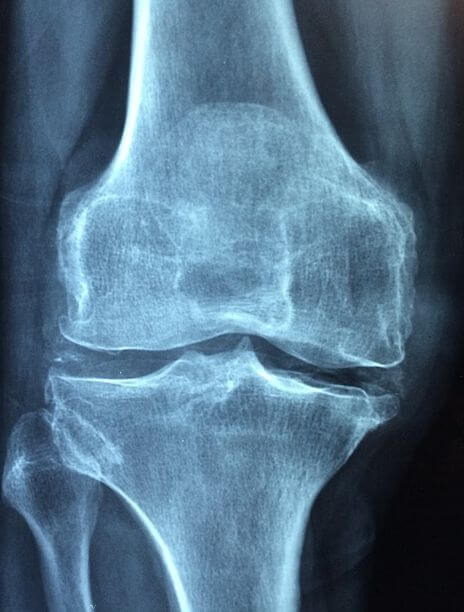

골밀도 검사는 방사선을 이용하여 우리 몸 특정 부위의 골밀도를 측정한 후 결과를 수치화하여 나타내는 검사입니다.

보통 에너지가 높은 X선과 에너지가 낮은 X선을 두 번 촬영하여 얻은 자료로 골밀도를 계산하는 이중에너지 X선 흡수 계측 법을 많이 사용합니다.

골밀도 측정을 통해 골다공증 및 골연화증을 조기에 발견할 수 있고, 골절의 치료 경과를 평가할 수 있습니다.

골다공증의 진단은 골밀도 측정을 이용하는데 측정한 골밀도를 젊은 성인의 정상 최대 골밀도와 비교한 값을 T 수치로 나타내어 평가기준에 의거 진단합니다.

* 정상 : T 수치가 -1 이상

* 골감소증 : T 수치가 -1~ -2.5 일 경우

* 골다공증 : T 수치가 -2.5 이하일 경우

X-ray 검사를 진행하여 골다공증으로 인한 압박 골절 등이 있는지도 알 수 있습니다.